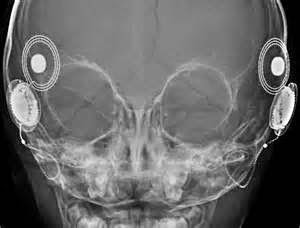

Not MY head.  I only have ONE implant.

Just before I left on vacation with my sons, I visited my surgeon’s office for my one-month, post-activation, check-up.  Aside from the fact that I was already wearing my cochlear implant, it was almost exactly the same as my activation visit one month earlier.  I saw the audiologist, we checked out all the electrodes in my head, tested for the loudest input I could tolerate, and then reprogrammed my devices with those new levels.